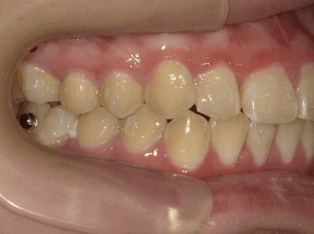

叢生(軽度)

BEFORE

AFTER

担当医コメント

上下に軽度の叢生がある。IPRと歯列の拡大で改善可能と考えインビザラインで治療を行うことにしました。

IPRは被せ物や銀歯の部位に集中させて、歯にかかる負担をなるべく少なくなるように計画した

治療の概要

年齢/性別

26歳 女性

主訴

上下の歯並びが気になる

リスク

歯肉退縮が起こる可能性がある。

費用

82万円(矯正費用)

期間

1 5 ヶ月